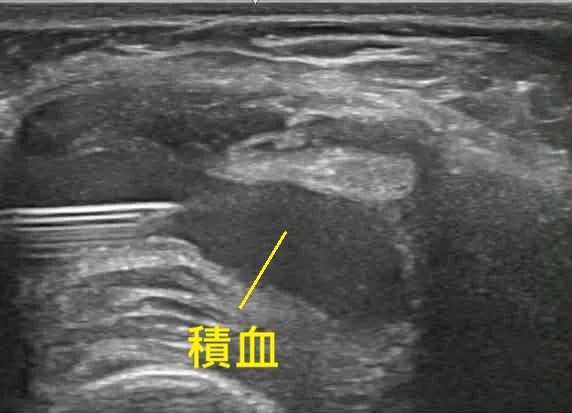

不是積水是「積血」!超音波下的紅色警訊

回到熟悉的診間,我立刻拿起超音波探頭檢查患部。影像顯示關節腔內有大量液體,但這液體的特徵與一般的發炎積水不同。

「這不是單純的積水,這是積血。」我看著螢幕,神色凝重地告訴他。

在骨科與復健科的臨床經驗中,膝蓋受傷若抽出的是血,事情往往不單純。這通常強烈暗示著關節內部結構的損傷,極高機率伴隨著韌帶斷裂或是半月板破裂。我們先將關節內的積血抽出以緩解腫脹與疼痛,並立即開立轉診單,安排他到醫院進行核磁共振 (MRI) 做進一步確認。